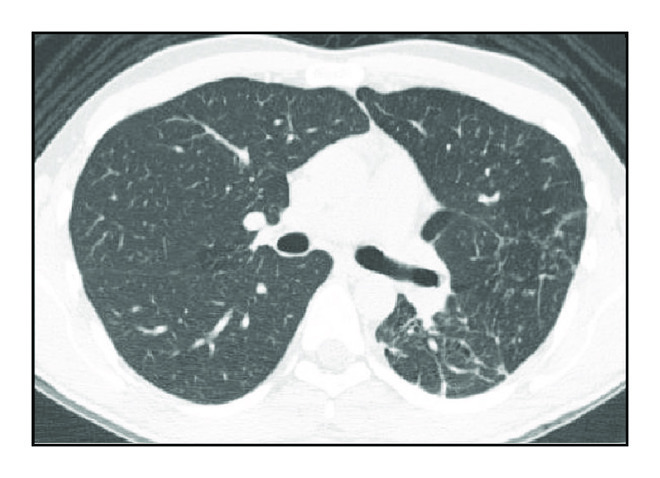

The analysis of CT2 followed the same methodology. There was an absolute predominance of airway changes characterized by cylindrical bronchiectasis, pulmonary parenchyma distortions, and 1–3 cm diameter nodules (Table 2 and Figure 2).

(a)

(b)

(c)

(d)

In CT2, we identified a high frequency of changes considered sequelae and diagnosed them as architectural distortion in 92% of cases and cylindrical bronchiectasis in 86% of cases. Thin-walled cavitary lesions and reduced injury volume have been reported in several studies as radiographic and tomographic criteria for successful treatment of TB [16–18]. We observed that cavitary lesions with wall thickness of <3 mm did not disappear. Of note, we found that 48% of cases had persistent nodules between 1 and 3 cm in diameter. These surprising but rarely reported data deserve to be recognized by doctors and underscore the need for interpreting image data within a known clinical context, avoiding diagnostic and therapeutic procedures sometimes unnecessary in patients already treated. Certainly, the large number of sequelae found, notably those associated with bronchiectasis and residual nodules known as tuberculomas, may be associated with the long duration of the disease and the late diagnoses.